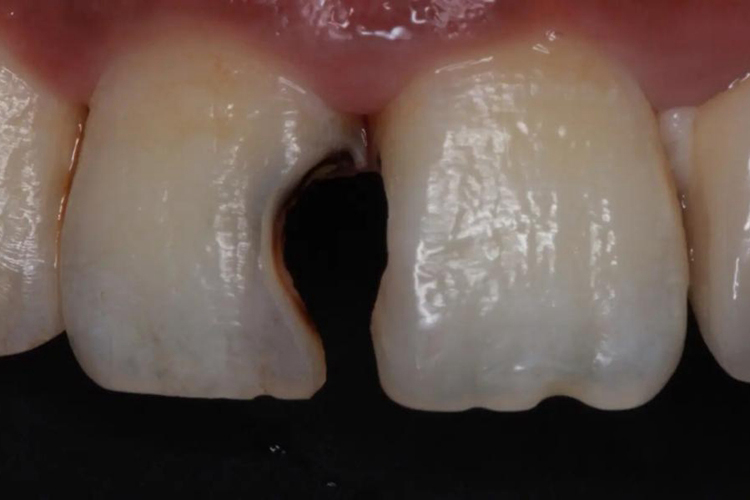

两颗门牙出现龋病时,牙体硬组织在色、形、质各方面均发生变化,包括牙颜色、光滑度和硬度的改变,随着病情进展可逐渐出现组织缺损。龋病可致使牙釉质呈白垩色,继之病变部位有色素沉着,局部呈黄褐色、棕褐色或黑色。病变早期可无自觉症状,若涉及牙本质,可导致患者进食冷热及酸性食物时出现患牙不适或酸痛。

若两颗门牙中间积聚有牙结石,外观呈黄白色、棕色或黑色,可因饮茶、吸烟、食物、药物等使颜色加重。牙结石可诱发或加重牙龈和牙周组织病变,引起牙龈组织出血及口腔异味等。